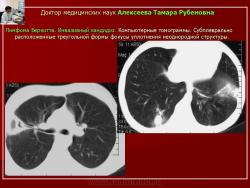

Рис. 13. Б-ной К. Лимфома Беркитта. Инвазивный кандидоз.

Обзорная рентгенограмма. В легких - различных размеров фокусы уплотнения с нечеткими контурами.

Рис. 14. Тот же б-ной К. Лимфома Беркитта. Инвазивный кандидоз

Компьютерные томограммы. Субплеврально расположенные треугольной формы фокусы уплотнения неоднородной структуры.